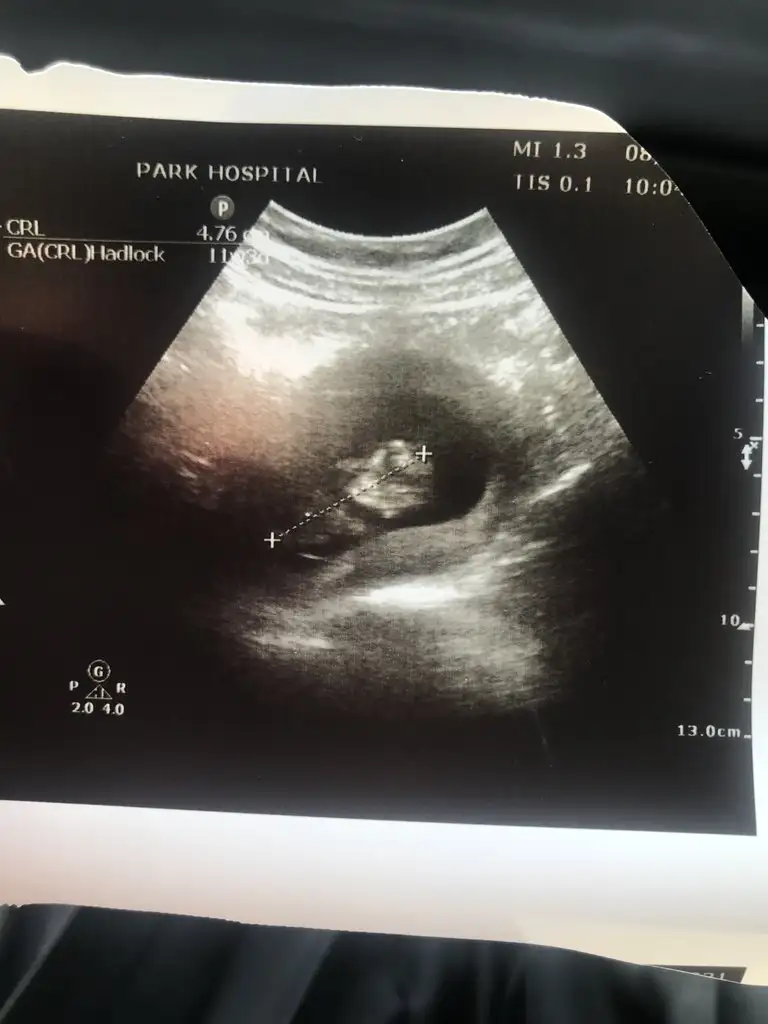

12+1iz :) bizede yorum yapan olur mu :)